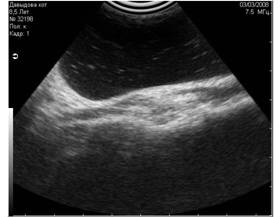

- сетевые - вызванные включёнием одновременно с УЗИ-аппаратом электрических приборов и сотовым телефоном (Рис.1; 2);

Рис1. Помехи, вызванные включённым рядом с аппаратом УЗИ сотовым телефоном. Во избежание этого лучше просить владельца выключать сотовый телефон при проведении ультразвукового исследования. |

Рис2. Помехи, вызванные работающими электроприборами, включёнными в сеть рядом с аппаратом УЗИ. |